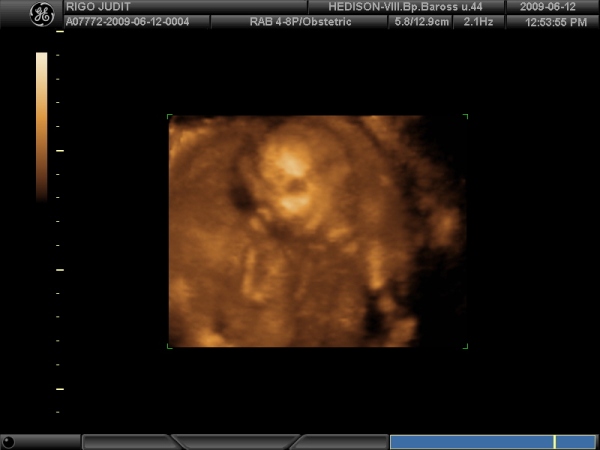

Megvolt szerdán a 4D uh. Nagyon szép élmény volt. Olyan kis eleven a mi kis babánk, hogy a dokinéni azt mondta, olyan mintha magyar táncot járna. Adott okot a neveteésre is, állítólag rögtön megmutatta, hogy KISLÁNY :) , aztán még többször is volt alkaloom ellenőrizni. Szóval mondta dokinéni, hogy erről a magamutogatásról gyorsan le kell szoktatni. :lol: . Mindene rendben van hála égnek.

Ime Miss Bogyó:

Kép

4,5 mm és a Szívecskéje 140-et ver, imádom!!!!!!!!!!!!!!!!